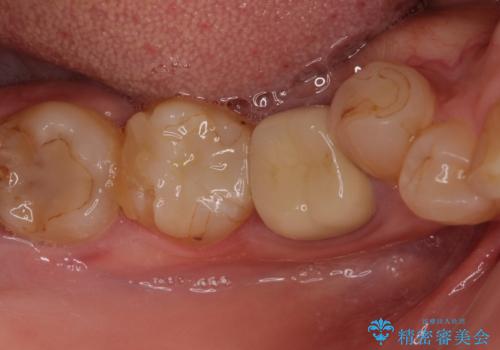

手前は根管治療後に補綴治療を、奥は骨造成後にインプラント埋入し、手前の歯と同時に補綴治療を行うこととしました。

歯槽骨の高さや幅を回復することができ、望ましい位置にインプラントを埋入することができました。